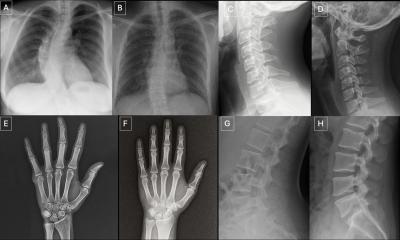

HRCT has become the first choice investigation for diagnosis of diffuse interstitial lung diseases with very fine anatomical resolution of the parenchyma,” she said. “Chest radiologists need to be pattern recognizers,”

Diagnosis is based on recognition of four major patterns: 1. the reticular pattern, 2. the nodular pattern, 3. increased density, which includes ground glass opacification and consolidation, and 4. decreased density. The course will advance from basic patterns based on anatomical details to more difficult patterns, and the subtype patterns that provide the basis for a differential diagnosis.